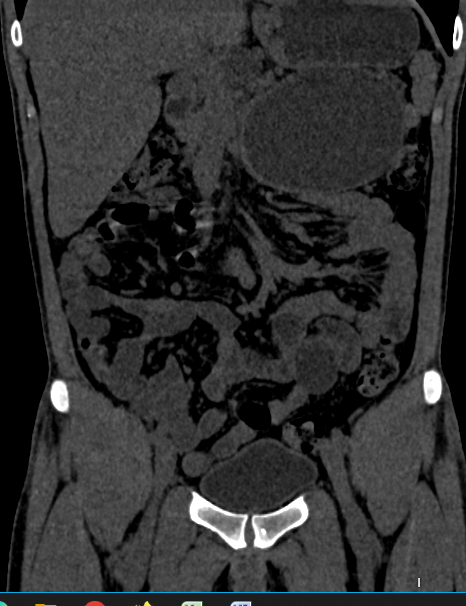

Right Kidney:

- Size and Shape: Measures 11.4 x 5.1 cm; normal in size and shape.

- Condition: Markedly dilated right renal pelvicalyceal system with abrupt narrowing at the pelvi-ureteric junction. Cortical atrophy noted.

- Calculi: Multiple varying-sized calculi in the lower calyx; largest measures 15 x 9 mm (HU value 900-1050).

- Perinephric Fat: Mild stranding noted.

Pancreatic Findings:

- Lesion: Well-defined rounded cystic hypoattenuating lesion, measuring approximately 11.3 x 8.3 x 7.8 cm (TRA x CC x AP).

- Location: Occupies the neck, body, and tail of the pancreas; inferior to the greater curvature of the stomach, anteroinferior to the spleen, and anterior to the upper pole of the left kidney.

- Impact: Abutting the greater curvature of the stomach and displacing the splenic vessels.

- Diagnosis: CT features suggestive of a pseudocyst of the pancreas.

Impression:

- Right Pelvi-Ureteric Junction Obstruction: Moderate hydronephrosis and cortical thinning.

- Multiple Right Renal Calculi

- Large Pancreatic Pseudocyst